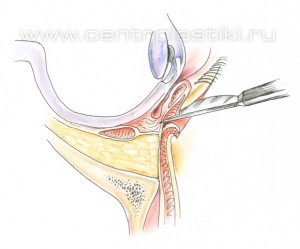

Рис. 6 Мышцу, аккуратно приподнимают и отделяют до края глазницы. Рис.7. Жировые «грыжи» опускаются вниз за край глазницы и фиксируются к надкостнице несколькими нитями, Рис. 8-9 таким образом, удается заполнить слезную и веко-щечную борозды Рис. 10.

Рис. 8